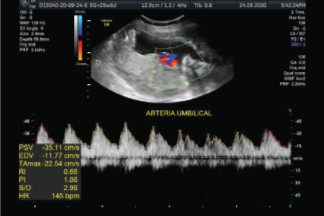

Permite ver el flujo sanguíneo de las arterias umbilicales del feto, de esta manera se puede saber si el flujo sanguíneo que llega al bebé es correcto, y por lo tanto también si lo son los nutrientes y el oxígeno que recibe el feto.